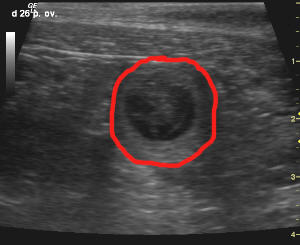

Hier ein paar von den Ultraschallbildern. Die mit rot umrandete Fläche ist ein h in seiner Hülle.